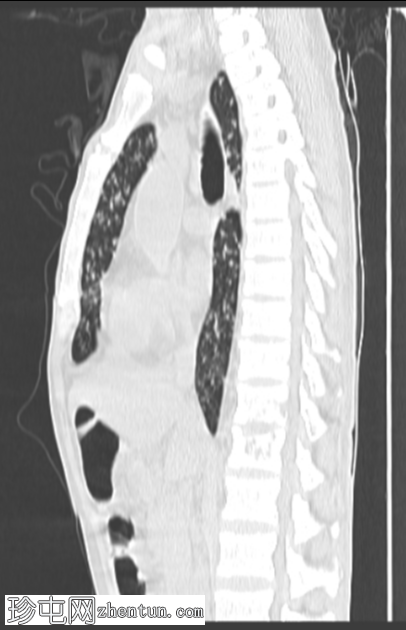

矢状肺窗

CT扫描图像:双侧肺部广泛粟粒性结节。

双侧肺部广泛粟粒性结节及树芽征,伴左上叶空洞及小气腔实变。